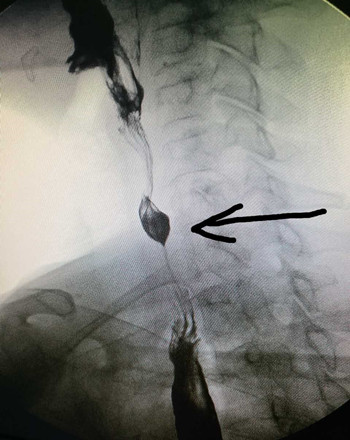

时隔1月,我科又于2017-03-06 17:00接诊了第二例食管异物患者。该患者于6小时前进食时误咽枣核,当时感咽部疼痛,无咳血及呼吸困难,无呛咳,进食时疼痛加重。门诊检查食道造影示:第7颈椎平面可见异物。门诊医师遂以“食道异物”收住入院。入院后张立刚副主任医师及刘教练主治医师立即安排各项术前工作,急查上消化道钡餐造影示:胸1椎体重叠处见梭形高密度影,结合食管造影,确定为食道异物。为防止患者出现食道感染及穿孔,遂急诊在全身麻醉下行食道异物取出术。用硬质食道镜直视下见食管入口下约2cm有一枣核,垂直扎入食管壁,有少许渗血,故异物钳夹住枣核后慢慢退出,检查食管壁无活动性出血后结束手术。从患者入院到手术结束,整个过程不到3小时。